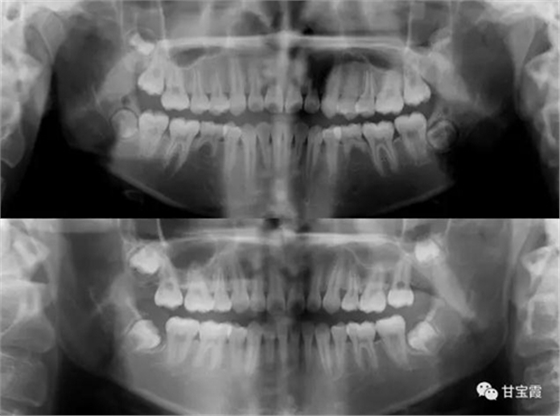

下面這兩張X片子就是矯正前后的對比,看不出下頜缺牙